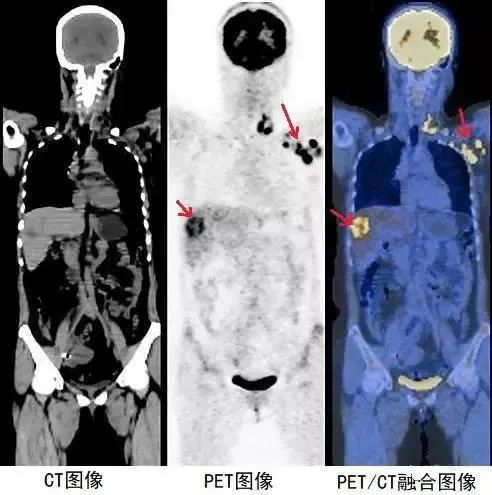

CT與PET的有機結合可將解剖結構影像與功能、代謝、生化影像精確重疊顯示,使醫生獲得最為全面的信息。

這對疾病的診斷,尤其是對腫瘤的診斷、定位和治療計劃有很大幫助。總而言之,CT與PET的結合PET/CT,是一個1+1大于2的技術整合。

PET/CT是PET和CT兩種掃描方式的融合,其圖像的生成是通過軟件將PET和CT獨立產生的兩種圖像配準進行融合得到的。